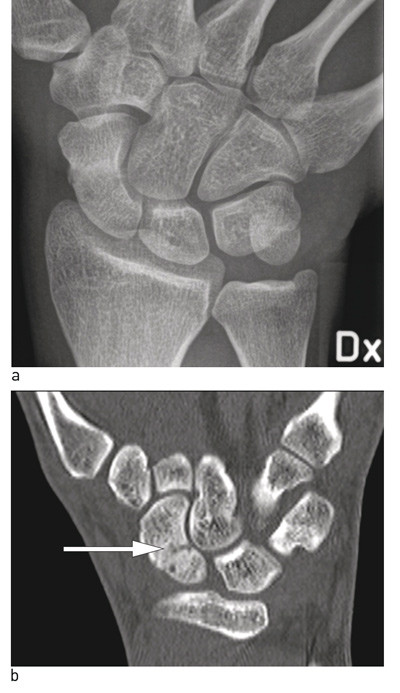

De fire radiologiske standardprojeksjonene (fig 2) avslører de fleste frakturer, men noen brudd er ikke synlige på initiale bilder. Pasienter med positive kliniske funn og negative funn på røntgenbilder må derfor følges videre. De kan enten avklares umiddelbart med MR/CT eller gipses og kontrolleres klinisk og røntgenologisk etter to uker. Ved fortsatt klinisk mistanke og negativt røntgenbilde tas CT eller MR slik at fraktur kan bekreftes eller avkreftes (fig 3). MR og CT har begge 100 % sensitivitet. CT vil bedre avsløre dislokasjon og tegn på eldre fraktur eller pseudartrose (10). Om man har mulighet, bør man avklare problemstillingen umiddelbart med supplerende bildediagnostikk, slik at pasienten slipper unødvendig gipsimmobilisering. Se flytskjema for utredning av mistenkt skafoidfraktur (fig 4).